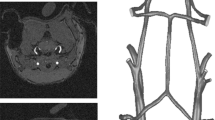

Vascular anatomy from the common carotid artery to a level distal to the circle of Willis was determined using three-dimensional phase-contrast MR angiography. Maximum intensity projections in orthogonal directions resulted in three-dimensional angiograms which were used to position the two-dimensional slice for the quantitative flow estimation (Q-flow, Philips Medical Systems) (Fig. 2A) and the labeling slice for quantitative CBF estimation (Fig. 2B).

(A) Coronal maximum intensity projections derived from phase-contrast angiography with indication of the slice for quantitative flow measurement in the internal carotid artery in a participant with T2DM. (B) Sagittal T1 weighted image with labeling slice (red), which was positioned at the same location of the slice for quantitative flow estimation, and imaging volume (green). (C) Resulting transverse CBF map. (D) Magnitude and (E) phase images of the carotid region, 1 left internal carotid artery, 2 left vertebral artery, 3 right internal carotid artery, 4 right vertebral artery.